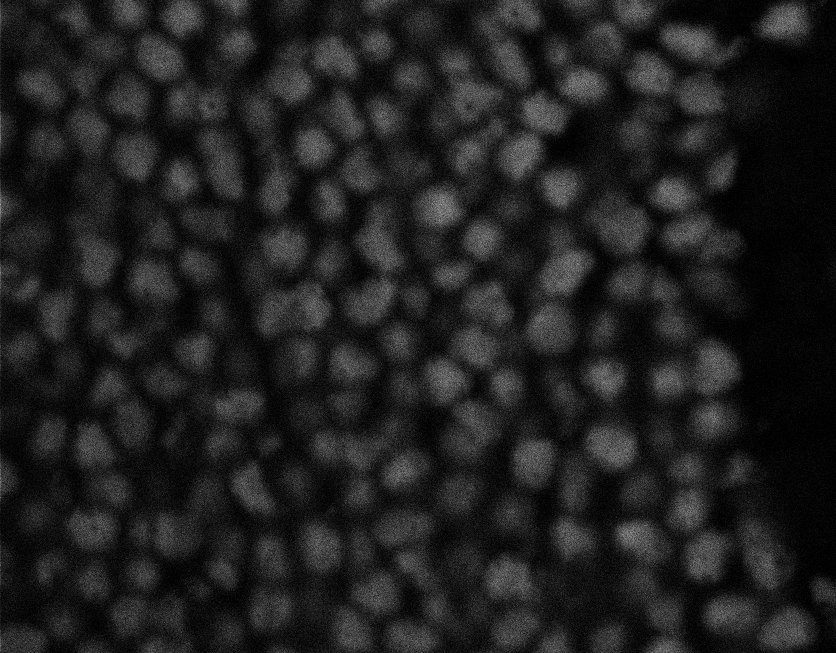

Nuclei

Nuclei - Bis

Nuclei - Bip

Nuclei - Bipolar